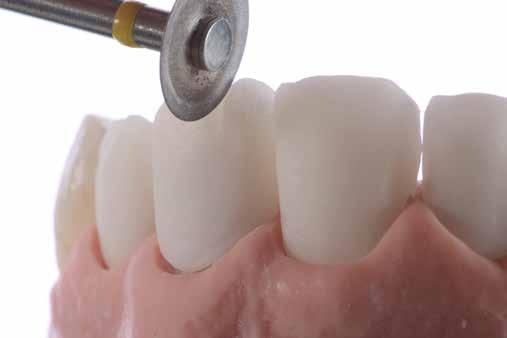

Ezt követően 6 hónapot vártunk a parodontális szövetek gyógyulásának érdekében. Ekkor a mock-up-ot felhelyeztük a páciens fogaira. Mivel a páciens elégedett volt a bemutatott látvánnyal, ezért a kezelés következő fázisának megkezdése mellett döntöttünk. A preparálás előtt a fogak felszínén mélységjelölő barázdákat alakítottunk ki (LVS1 FG Medium Depth Cutting Diamond 834.31.021, Brasseler Dental, One Brasseler Boulevard Savannah, Georgia 31419, Egyesült Államok). A megfelelő anyagvastagság biztosításához ezen felül egy 0,5 mm vastagságú átlátszó redukciós sablont (Keystone Industries, 480 South Democrat Road, Gibbstown, New Jersey, Egyesült Államok) is készítettünk. A sablont egy vákuumkészülék (Pro-Vac Machine 110V, Keystone Industries) segítségével hoztuk létre. A protetikai fázis során a frontfogak és az első kisőrlőfogak kerámia héjakkal történő ellátását terveztük. A preparálás mélységét a sablon felhelyezését követően, a sablonon lévő perforációk segítségével tudtuk ellenőrizni. A nyílásokba parodontális szondát vezettünk, hogy meghatározzuk a redukció mértékét (6. ábra). A preparálás megfelelőségét ezen felül egy gyúrható szilikonból készült sablonnal is ellenőriztük. Ebben az esetben is parodontális szondát használtunk a mélység ellenőrzése céljából (6. ábra). A csonkelőkészítés utolsó lépéseként a lecsiszolt fogfelszíneket polírkorongok segítségével (OptiDisc, Kerr, Orange, Kalifornia, Egyesült Államok) simára políroztuk. A lenyomatvétel során duplafonalas lenyomatvételi technikát alkalmaztunk. Az ínybarázdákba először #00-

8. ábra. Az ultravékony héjak adhezív módszerekkel történő ragasztása. (A): Az elkészült héjak. (B): A fogfelszínek kofferdám izolálásban történő foszforsavas kondicionálása. (C): Az adhezív felvitele. (D): A héjak fényre kötő rezin alapú ragasztócementtel történő ragasztása.

ás, majd #0-ás retrakciós fonalakat (Ultrapak, Ultradent Products Inc, South Jordan, Utah, Egyesült Államok) helyeztünk. A végső precíziós lenyomatot polivinil-sziloxán lenyomatanyaggal (Virtual 380, Ivoclar Vivadent AG, Schaan, Liechtenstein) vettük. A fogtechnikai fázisban ultravékony (0,5 mm-nél vékonyabb) földpátkerámia héjak elkészítését kértük (Super Porcelain Ex-3, Kuraray Noritake Dental, Tokió, Japán), (7. ábra). A kerámia héjak készre vitelét követően a próba során a héjakat a helyükre illesztettük a széli zárást, az így kialakított fogformák ellenőrzése céljából. A páciens elégedett volt az így kapott látvánnyal. A végleges ragasztás kofferdám izolálásban történt. A preparált fogak felületét először 37%-os foszforsavval (Total Etch, Ivoclar Vivadent) 15 másodpercen keresztül kondicionáltuk, majd vízzel leöblítettük (8. ábra). A kondicionált zománcfelszíneket Adhese Universal (Ivoclar Vivadent) adhezívvel kezeltük. A kerámiahéjak homorú felszíneit 5%-os folysavval (IPS Ceramic Etching Gel, Ivoclar Vivadent) 20 másodpercen át kondicionáltuk, majd a felszíneket Monobond Plus primerrel (Ivoclar Vivadent) vontuk be (7. és 8. ábrák). A héjakat fényre kötő rezinalapú ragasztócement (Variolink Esthetic LC, Ivoclar Vivadent) applikálását követően a helyükre illesztettük. A kifolyó cementfelesleg eltávolítását követően minden felszínt (labiális, palatinális, meziális és distális) LED-es polimerizációs lámpával (VALO Cordless, Ultradent) 40 másodpercen keresztül megvilágítottuk.